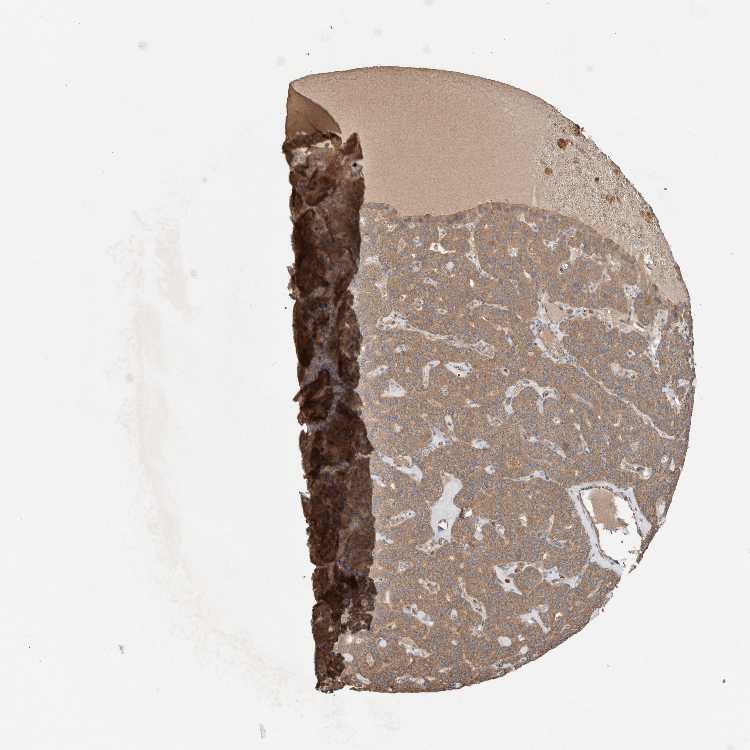

PARATHYROID GLAND - Antibody stainingi

Antibody staining in the annotated cell types in the current human tissue is reported as not detected, low, medium, or high, based on conventional immunohistochemistry profiling in selected tissues. This score is based on the combination of the staining intensity and fraction of stained cells.

Each image is clickable and will lead to virtual microscopy that enables deeper exploration of all samples and also displays staining intensity scores, fraction scores and subcellular localization as well as patient and tissue information for each sample.

Antibody CAB026228

Glandular cells Medium